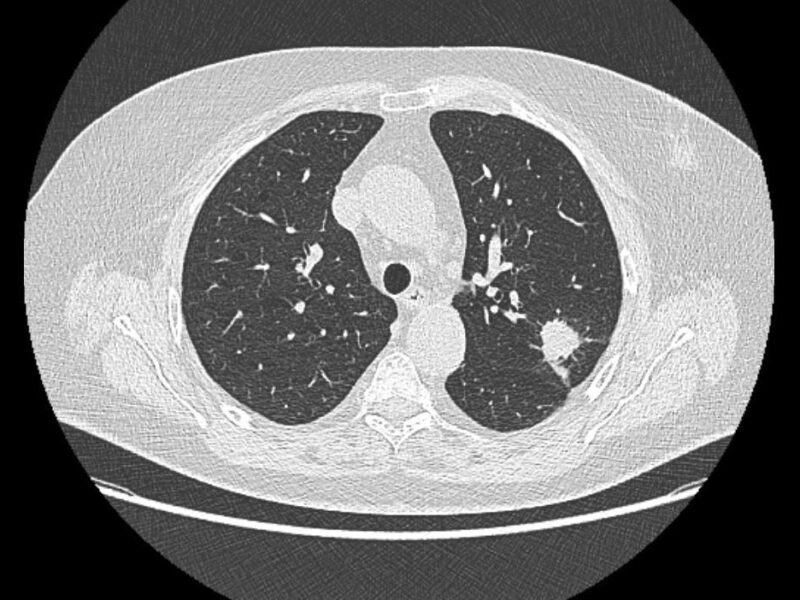

Aux États-Unis, les médecins de UC San Diego Health, associés à Amazon Web Services, évaluent l’efficacité chez les patients COVID d’un algorithme développé par leurs soins pour détecter la pneumonie sur des radiographies du thorax. « Environ 75 % des patients COVID-19 positifs hospitalisés développent une pneumonie virale, rappellent-ils dans la revue Journal of Thoracic Imaging [2]. La détection rapide de la pneumonie chez ces patients pourrait permettre une application rapide de